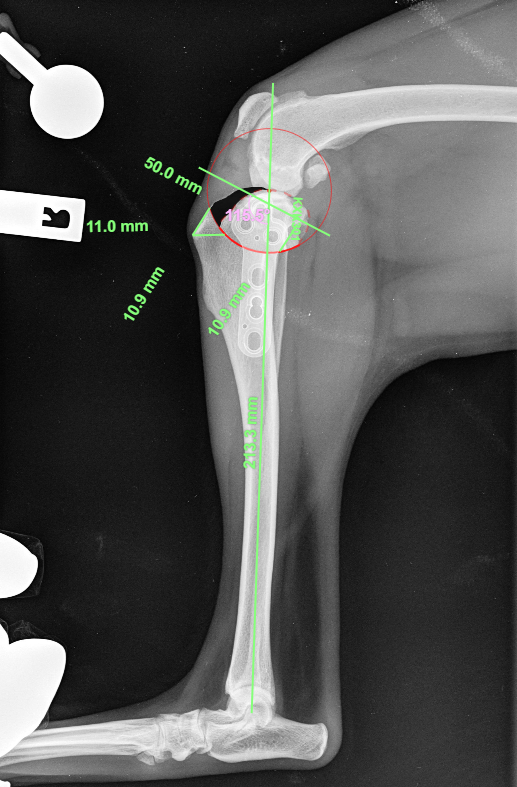

Radiograph of a dog knee joint - a canine stifle - with lines and angles showing the measurements and planning necessary for Stifle Surgeons to perform a TPLO for cruciate rupture in a dog.

TPLO, lateral suture, MPL correction

• Procedures: TPLO, extracapsular (lateral suture) stabilisation, tibial tuberosity transposition (TTT), trochleoplasty and more